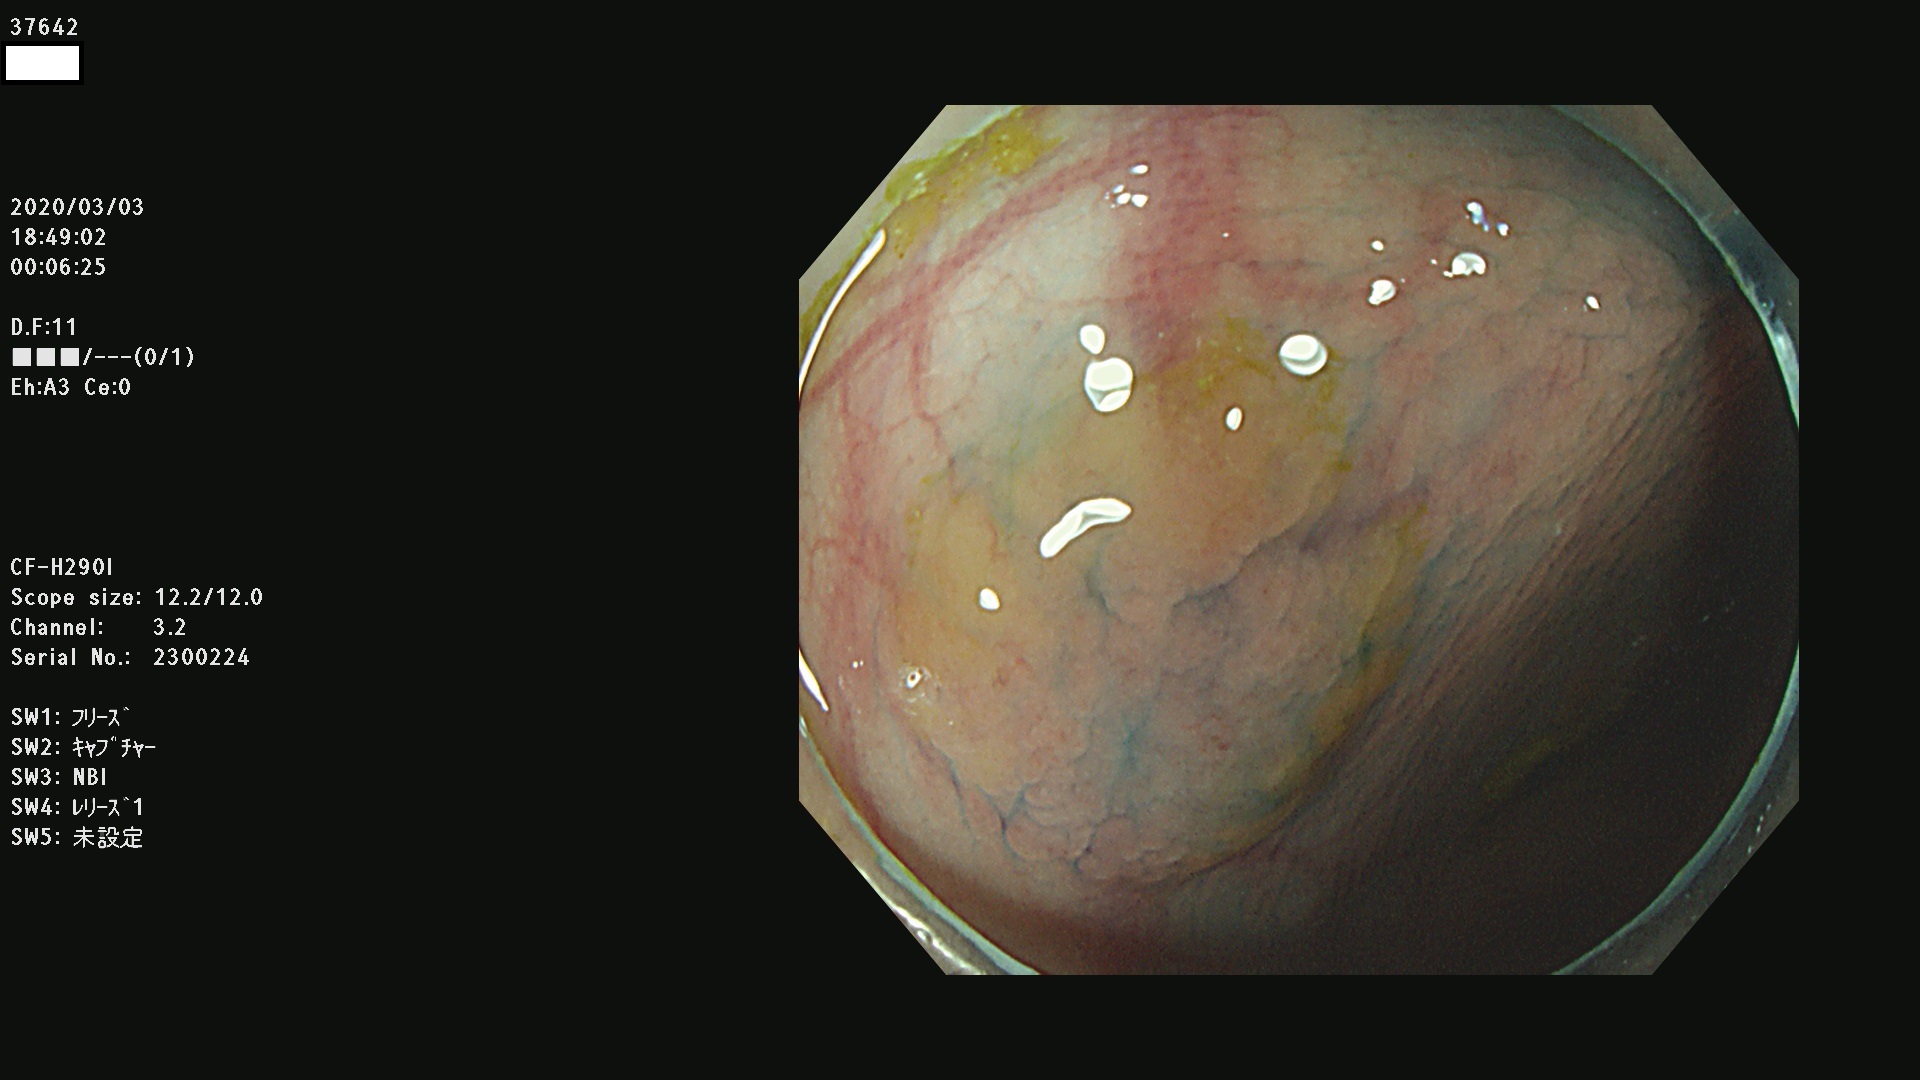

37600 37601 37602 37603 37604 37605 37606 37607 37608 37612 37614 37616 37618 37619 37620 37621 37622(SSAPのみ) 37623(SSAPのみ) 37624 37626 37627 37628 37629 37632 37633 37635 37636(SSAPのみ) 37639 37640 37641 37642 37643 37644 37647(SSAPのみ) 37648 37649 37650 37652 37653 37655 37657 37659 37660 37662 37664 37666 37668(SSAPのみ) 37670 37671 37672 37676 37677 37678 37679 37680 37682 37684 37685(SSAPのみ) 37686 37687 37688 37689 37690 37691 37692(SSAPのみ) 37693 37694 37695 37696 37697 37699

発見困難で危険性の高い平坦型病変(上記100名より抽出)